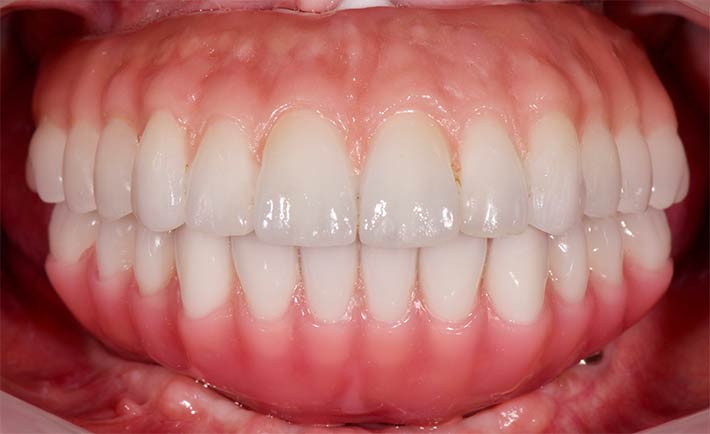

最終補綴 上顎:フルジルコニアタイプ/下顎:人工歯タイプ

顎骨が高度に吸収されている本症例においても、物が詰まりづらく発音しやすい最終補綴装置を提供しております。その為には術前の治療計画から、仮歯の調整まで全てのステップを丁寧に行うことが重要です。